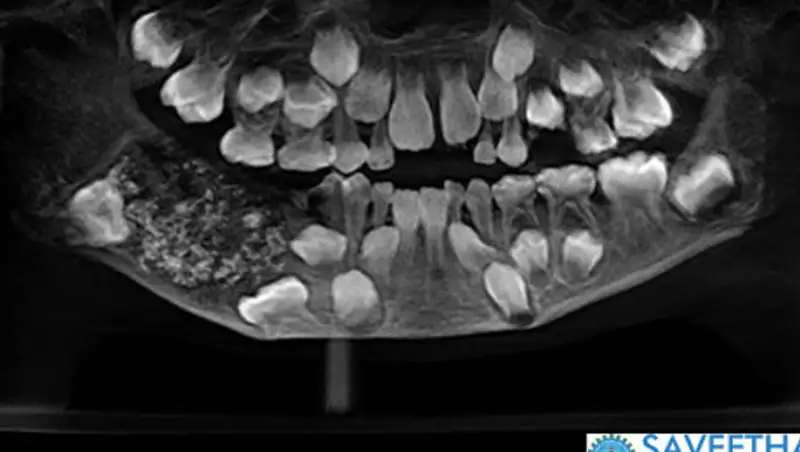

В Индии врачи удалили семилетнему ребенку 526 лишних зубов, сообщает РИА новости со ссылкой на Times of India.

Мальчик жаловался на сильную боль в нижней челюсти. Компьютерная томография и рентген показали, что во рту у ребенка опухоль с огромным количеством мелких рудиментарных зубов. Врачи настояли на немедленной операции и за несколько часов удалили нарост. В настоящее время ребенок чувствует себя хорошо.

Причина такой аномалии не ясна. Врачи допускают, что это может быть генетическое заболевание, однако не исключают и версию воздействия излучения от сотовой вышки. В последний раз индийские медики сталкивались с похожим случаем в 2014 году, тогда пациенту удалили 232 зуба.